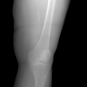

In this section, we provide qualitative and quantitative results of the two proposed diffusion-based methods and compare them with the baseline U-Net model. The first column of Fig. 3 showcases six randomly selected conditions: (a0)-(c0) show contour segmentations, and (d0)-(f0) denote segmentations containing contour and bones. In Fig. 3 (a1)-(f1), the images generated by U-Net contain blurred fine details in locations where bones overlap, despite maintaining the given shape, as highlighted by the red circle. In contrast, the results from CSM appear more realistic than the U-Net. However, their quality decreases with introduced constraints, as indicated by the red arrow in Fig. 3 (d2) and (f2). The results from CTM not only achieve nearly the same level of fineness as the labels but also provide reasonable results with respect to the given conditions as illustrated in the fourth column.